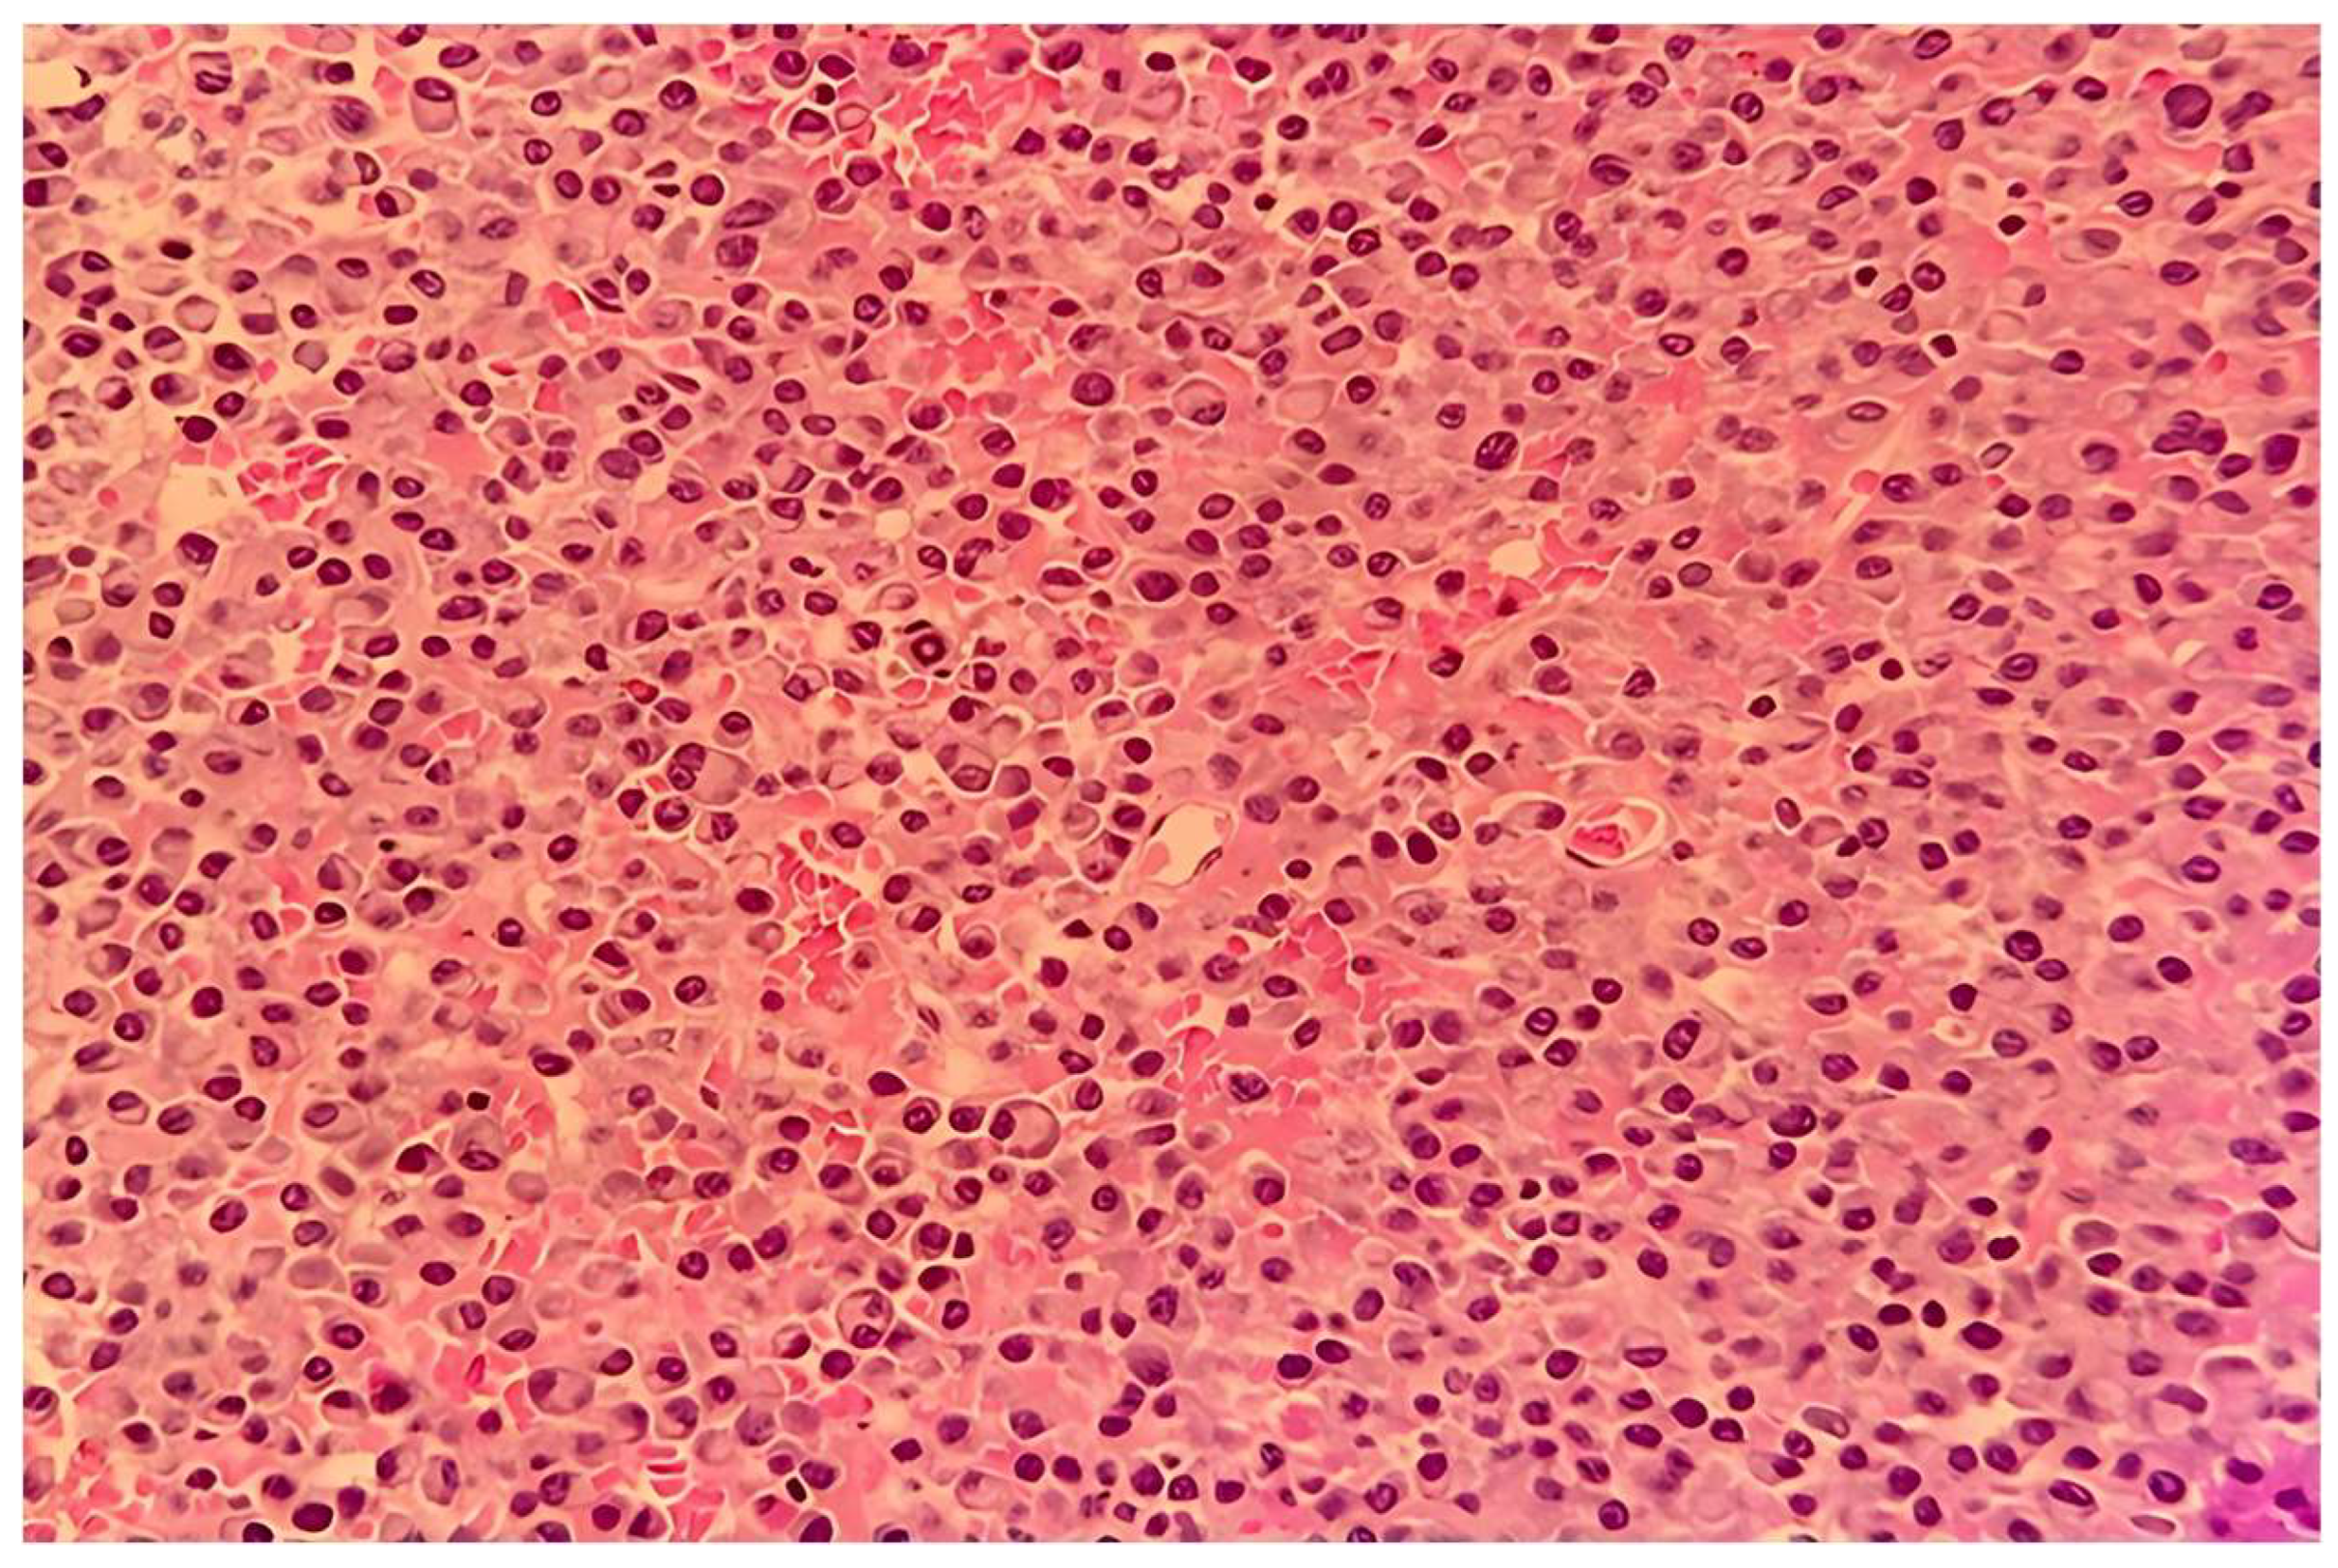

| Histopathology | Plasmacytoid cells, hemorrhage | Plasmacytoid cells, necrosis | Compact eosinophilic cells |

| Immunohistochemistry | CD38+, CD138+ | CD79a+, CD138+, CD56+ | CD138+ |